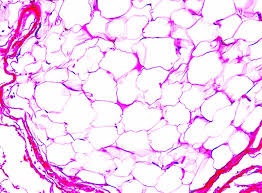

Histology: What Does a Lipoma Look Like Under the Microscope?

Histology refers to how tissue appears when examined microscopically.

Under the microscope, a lipoma shows:

-

Mature adipocytes (fat cells) that look identical to normal body fat

Cells arranged in lobules

A delicate fibrous connective tissue framework

No cellular atypia, abnormal nuclei, or aggressive features

This normal cellular appearance is what confirms a lipoma’s benign nature.